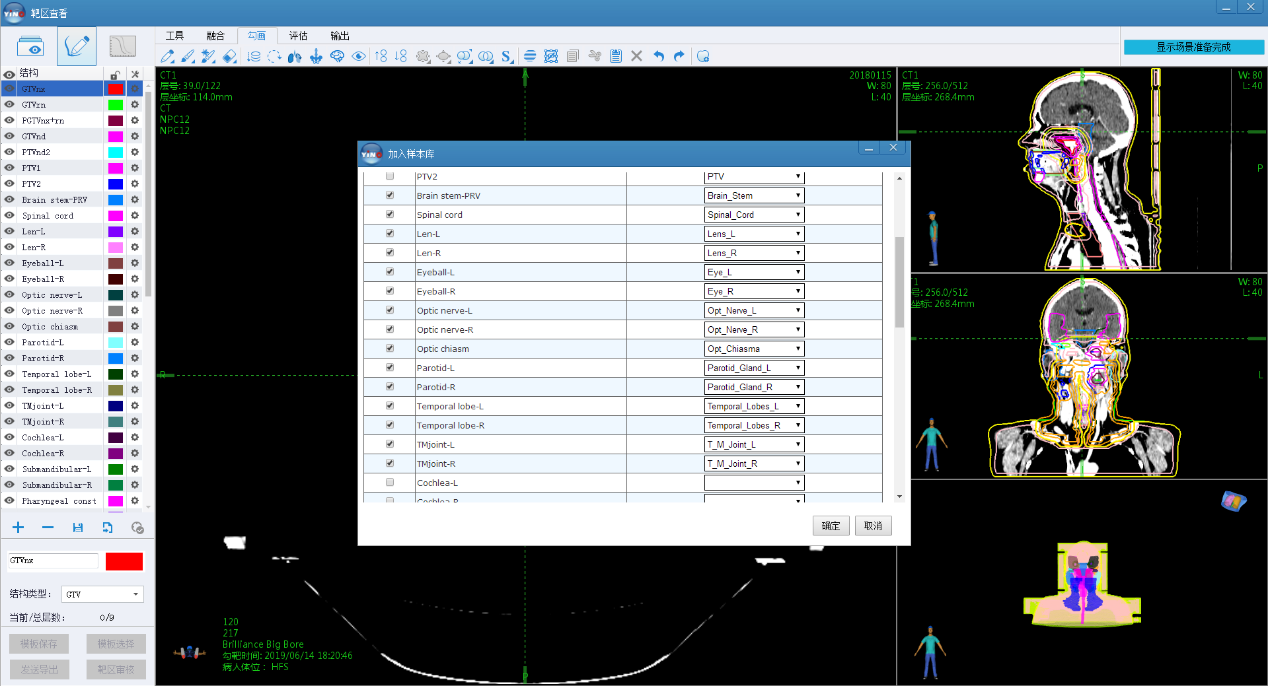

дёәжҠөиҫҫд»ҘдёҠеӨ§дјҡи§’йҖҗиҰҒжұӮ���пјҢhjc888й»„йҮ‘еҹҺиҝһзі»иҮӘиә«жүӢиүәдјҳеҠҝдёәеӨ§дјҡжҸҗдҫӣдәҶеӨҡеҘ—е®Ңе…ЁиҮӘдё»з ”еҸ‘зҡ„дә§е“ҒдёҺжүӢиүәе№іеҸ°���пјҢеҢ…жӢ¬е…·еӨҮиҮӘжҲ‘еӯҰд№ еҠҹж•Ҳзҡ„ж”ҫз–—з—…жЎҲж•°жҚ®иҮӘеҠЁеҢ№й…ҚдёҺж ҮеҮҶеҢ–еӨ„зҪ®жғ©зҪҡзі»з»ҹгҖҒеҸҜеҜ№ж”ҫз–—з—…жЎҲж•°жҚ®з»“жһ„еҢ–иҮӘеҠЁе®Ўж ёдёҺ专家йҮ‘ж ҮеҮҶеҸ еҠ иҜ„дј°зҡ„ж”ҫз–—еӢҫз”»дәӢжғ…з«ҷ���пјҢд»ҘеҸҠеҸҜзҹҘи¶іеӨҡиҫҫ500дҫӢз—…дҫӢеҗҢж—¶еңЁзәҝз”ұж•°еҚҒдҪҚ专家еҸҜйҡҸж—¶жҒЈж„ҸеҲҮжҚўе№¶еңЁзәҝиҜ„е®Ўзҡ„жүӢиүәеҚҸдҪңж•ҲеҠіе№іеҸ°�����гҖӮ

hjc888й»„йҮ‘еҹҺж”ҫз–—з—…жЎҲж•°жҚ®иҮӘеҠЁеҢ№й…ҚдёҺж ҮеҮҶеҢ–еӨ„зҪ®жғ©зҪҡзі»з»ҹ

hjc888й»„йҮ‘еҹҺж”ҫз–—з—…жЎҲж•°жҚ®з»“жһ„еҢ–иҮӘеҠЁе®Ўж ёдёҺ专家йҮ‘ж ҮеҮҶеҸ еҠ иҜ„дј°зҡ„ж”ҫз–—еӢҫз”»дәӢжғ…з«ҷ

еҠҹж•ҲејәзӣӣеҸҜз”ЁдәҺеӨҡеҢ»йҷўй—ҙиҝңзЁӢеҚҸдҪңзҡ„hjc888й»„йҮ‘еҹҺж”ҫз–—еҚҸдҪңжүӢиүәе№іеҸ°

йңҖиҰҒзү№ж®ҠжҢҮеҮәзҡ„жҳҜ���пјҢCSTROж”ҫз–—AIеӢҫз”»еӨ§иөӣ组委дјҡжҸҗеҮәйқўйўҲOARsгҖҒйј»е’ҪзҷҢGTVгҖҒиғёйғЁOARsгҖҒиӮәзҷҢGTVеӢҫз”»4дёӘи§’йҖҗ科зӣ®йғҪиҰҒеңЁзҺ°еңәдёҫиЎҢAIеӢҫз”»ж•Ҳжһңеұ•зӨә���пјҢ并确дҝқеҗҢж—¶жҜҸдёӘAIеӢҫз”»ж•ҲжһңйғҪиҰҒе’Ң专家еӢҫз”»зҡ„йҮ‘ж ҮеҮҶдёҫиЎҢеҸ еҠ жҜ”з…§жҳҫзӨә���пјҢиҝҷе°ұиҰҒжұӮhjc888й»„йҮ‘еҹҺжҸҗдҫӣзҡ„жүӢиүәж•ҲеҠіе№іеҸ°йңҖиҰҒеҢ…з®Ўиҝ‘500дҫӢз—…дҫӢпјҲжҜҸдёӘз—…дҫӢеҢ…жӢ¬100еӨҡеј CTеӣҫеғҸе’ҢеӨ§е®—зҡ„з»“жһ„иҪ®е»“зәҝе…ұи®Ў50000еј CTеҪұеғҸзӯүе®Ңж•ҙзҡ„з—…дҫӢдҝЎжҒҜпјүиҰҒеҗҢж—¶еңЁе№іеҸ°дёҠе®һж—¶еҗҢжӯҘйЎәз•…иҝҗиЎҢ�����гҖӮдҪңдёәжҳҫи‘—жҜ”з…§зҡ„жҳҜ���пјҢзҺ°еңЁеңЁеҗ„еҢ»йҷўж”ҫз–—дёӯеҝғе№іж—¶дҪҝз”Ёзҡ„еҢ»з”ҹдәӢжғ…з«ҷжҲ–жІ»з–—еҰ„жғізі»з»ҹпјҲTPSпјүжқҘеұ•зӨәеӢҫз”»ж•Ҳжһң���пјҢдёҖж¬ЎеҸӘиғҪзҝ»ејҖдёҖдҫӢз—…жЎҲ���пјҢдёҖж ·е№іеёёзҡ„еҢ»з”ҹдәӢжғ…з«ҷзҝ»ејҖдёҖдёӘз—…дҫӢйҖҡеёёйғҪйңҖиҰҒеҮ еҚҒз§’жүҚеҚҺеңЁиҪҜ件з•ҢйқўжҳҫзӨәеҮәжқҘ�����гҖӮhjc888й»„йҮ‘еҹҺдҫқжүҳеңЁж·ұиҖ•ж”ҫз–—еҚҒдә”е№ҙзҡ„жүӢиүәз§ҜзҙҜдёҺдә§е“ҒдјҳеҠҝ���пјҢжү“йҖ дәҶеҸҜе®№зәіеӨҡ家зӣёеҠ©еҢ»йҷўдёҺ专家еҗҢж—¶еңЁзәҝжҸҗдҫӣиҝңзЁӢж”ҫз–—еҚҸдҪңзҡ„жүӢиүәж•ҲеҠіе№іеҸ°���пјҢеҫҲеҘҪзҡ„зҹҘи¶ідәҶжң¬ж¬ЎеӨ§иөӣзҡ„иҰҒжұӮ���пјҢеҸҜд»ҘдёҖж¬ЎжҖ§еҝ«йҖҹзҝ»ејҖ500дҫӢеҢ…жӢ¬еҮҢй©ҫ5дёҮеј й«ҳжё…CTеҪұеғҸж•°жҚ®зҡ„еӢҫз”»з—…жЎҲ���пјҢ并иғҪеӨҹзҹҘи¶іеҮ еҚҒеҗҚ专家еҗҢж—¶еңЁ500дҫӢAIеӢҫз”»ж•Ҳжһңд№Ӣй—ҙдёҫиЎҢжҒЈж„ҸеҫҖиҝ”еҲҮжҚў���пјҢжҜҸж¬ЎеҲҮжҚўз—…жЎҲеқҮдёҚеҲ°1з§’ж—¶й—ҙеҚіеҸҜйЎәз•…е®ҢжҲҗ�����гҖӮ